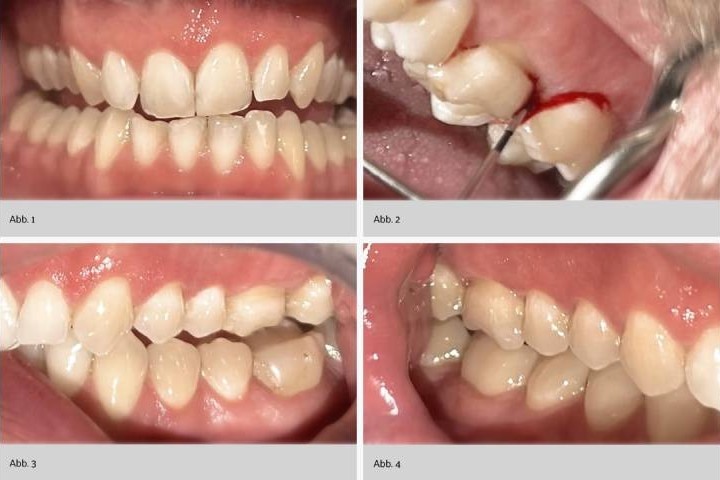

Abb. 5: Die Abbildungen 1 bis 5 zeigen die klinische Ausgangslage des vorgestellten Patientenfalls (männlicher Patient in den 40ern, Raucher) vor der Umstellung auf meridol Parodont Expert-Produkte. Es zeigen sich generalisierte, ausgeprägte Entzündungszeichen. Dazu zählen klinische Zeichen wie Rötung und Schwellung (Abb. 1). An Zahn 26 distal zeigt sich eine Sondierungstiefe von 5 Millimetern mit positivem Bleeding on Probing (Abb. 2). Die Ansichten der Seitenzahnbereiche zeigen Zeichen einer generalisierten Entzündung mit geröteter und geschwollener Gingiva (Abb. 3 und 4). Der klinische Status vor der Umstellung auf meridol Parodont Expert-Produkte dokumentiert generalisierte BOP-positive Stellen sowie Sondierungstiefen von bis zu 5 Millimetern und damit generalisierte Zeichen einer aktiven parodontalen Entzündung (Abb. 5).

Ein männlicher Patient in den 40ern mit einer 25-pack-years-Tabakanamnese wurde seit Jahren halbjährlich dentalhygienisch betreut. Die Behandlung erfolgte mittels Ultraschall, Air-Polishing und Handinstrumenten. Trotz guter häuslicher Mundhygiene (Schallzahnbürste mit mittelhartem Kopf zweimal täglich zwei Minuten, Kunststoff-Interdentalbürsten einmal täglich, verschiedene desensibilisierende Sensitive-Zahnpasten) zeigten sich persistierende parodontale Taschen bis 5 mm mit ausgeprägter Blutung (BOP) besonders regio 26 distal (Abb. 1 bis 4 und 7).

Der Patient berichtete über unangenehmen Geschmack im Mund, häufiges Zahnfleischbluten sowie Dentinhypersensibilität. Chlorhexidinprodukte wurden aufgrund von Nebenwirkungen nicht vertragen. Radiologisch zeigte sich kein signifikanter Knochenabbau, klinisch jedoch beginnender Attachmentverlust unter Anderem regio 26 (Abb. 5 bis 7).